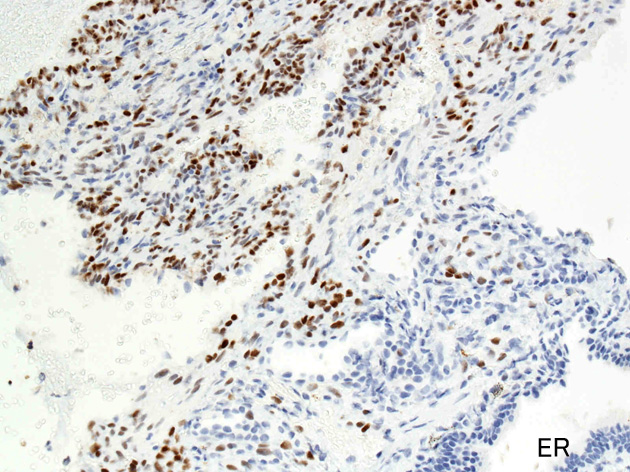

ER.jpg

PgR.jpg

Estrogen receptorProgesteron receptor